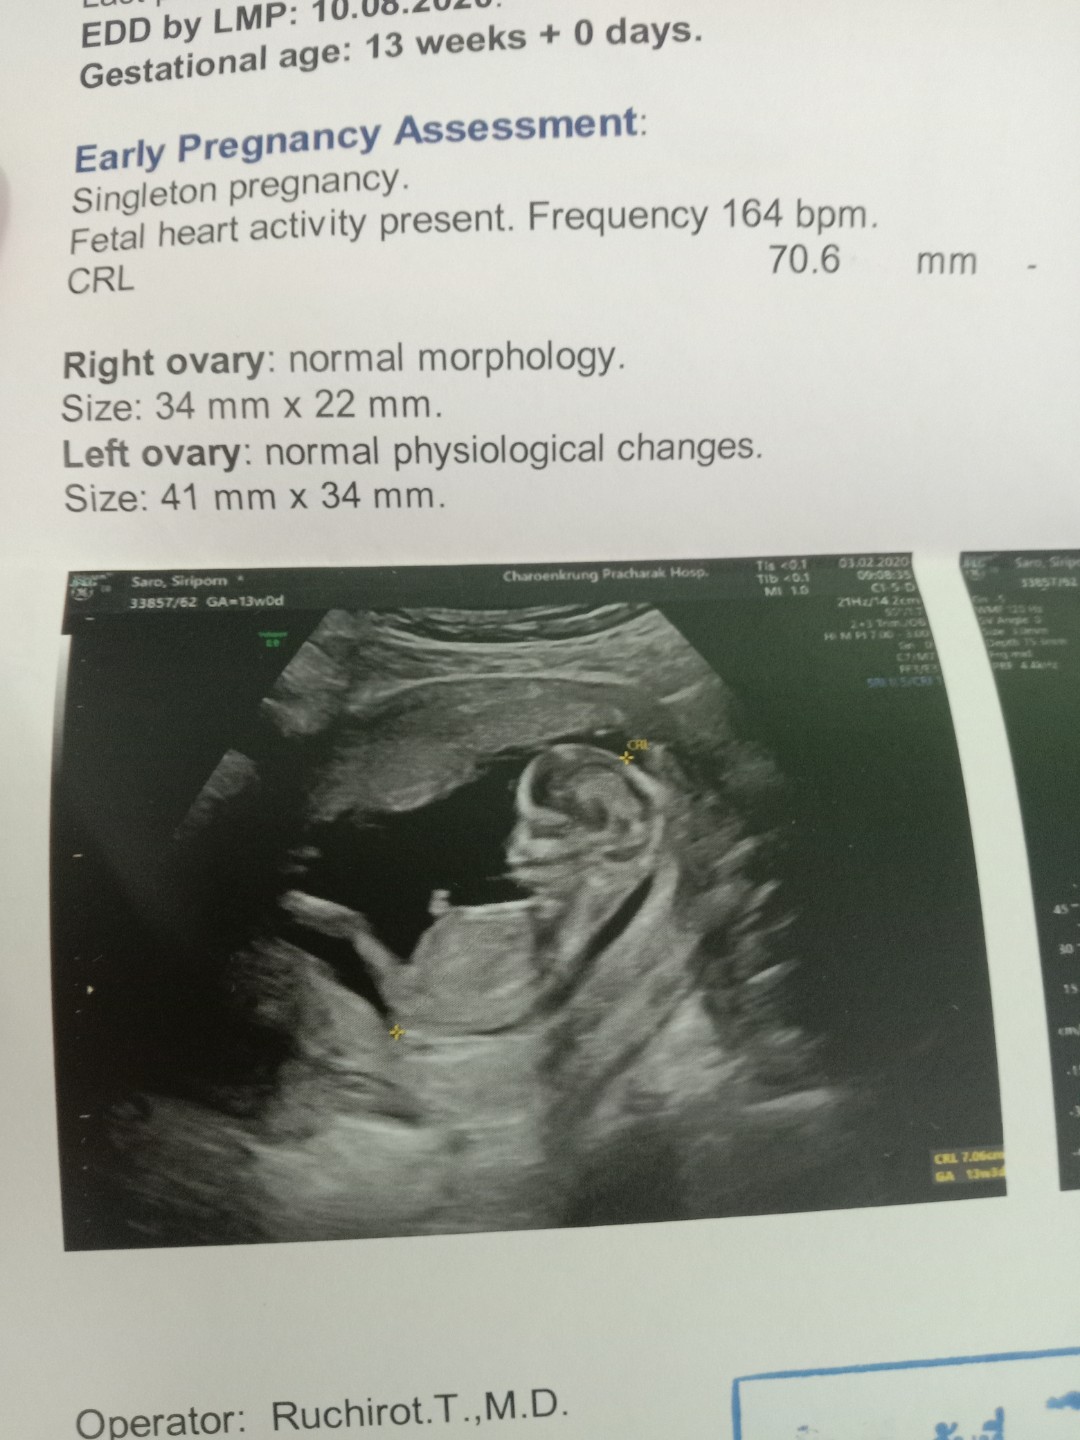

13 weeks ka